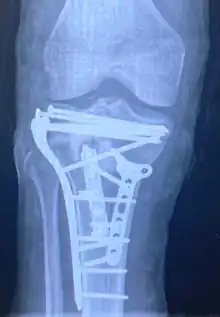

Pain may be managed with NSAIDs, opioids, and splinting.[1][2] In those who are otherwise healthy, treatment is generally by surgery.[1] Occasionally, if the bones are well aligned and the ligaments of the knee are intact, people may be treated without surgery.[2] The surgery usually involves reducing the fractured fragments of the tibia plateau to their anatomical position and fixing them in place with screws only or fixed angle anatomical plates ensuring absolute stability. Implant selection is based on the type of injury. Generally, simple or incomplete fractures (Schatzker type 1) of the plateau are compressed with 6.5mm partially threaded cancellous screws. Complex type fractures will require a plate for enhanced stability. As the tibia condyles articulate with the femur (thigh bone) to form knee joint, any incongruity in the articular surface is unacceptable as it leads to early arthritis. Prolonged immobilization of the knee joint is also not recommended which result in stiffness of the joint and difficult recovery. It's currently debated what role primary total knee arthroplasty (Joint Prosthesis) plays in the treatment of tibial plateau fractures. Although accompanied with risks small studies have shown promising results.[9]